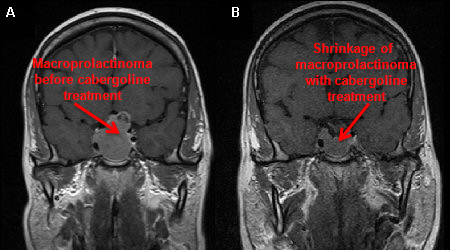

Post-menopausal women with microadenoma or undetectable pituitary mass do not usually require any treatment. Galactorrhoea usually improves when endogenous oestrogen decreases post-menopausally.[Figure caption and citation for the preceding image starts]: Gadolinium-enhanced magnetic resonance imaging (coronal view) showing a 40 mm pituitary macroprolactinoma in a 41-year-old man before (A) and after (B) 2-month treatment with cabergolineFrom the collection of Dr Ilan Shimon [Citation ends].

[Figure caption and citation for the preceding image starts]: Gadolinium-enhanced magnetic resonance imaging (sagittal view) showing a 40 mm pituitary macroprolactinoma in a 41-year-old man before (A) and after (B) 2-month treatment with cabergolineFrom the collection of Dr Ilan Shimon [Citation ends].